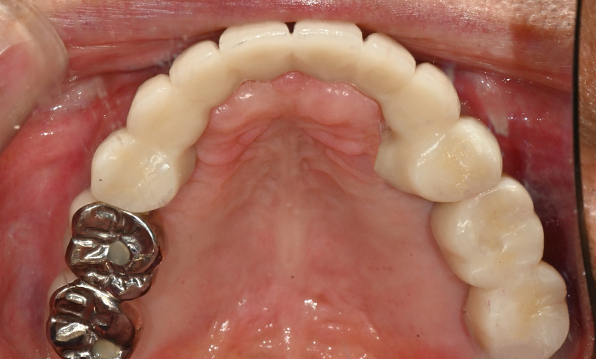

성공을 위한 노하우, 잇몸뼈 재건 기술

전체 임플란트를 해야하는 환자들은

대부분 고령의 환자들로 오랜 틀니 사용

또는 노화로 인해 치조골이

거의 남아있지 않는 경우가 많습니다.

이 때, 치조골 이식을 병행하여 잇몸뼈 재건 후 안정적인 임플란트 식립을 하고 있습니다.

치료기간 : 2021.04.12~2021.09.15